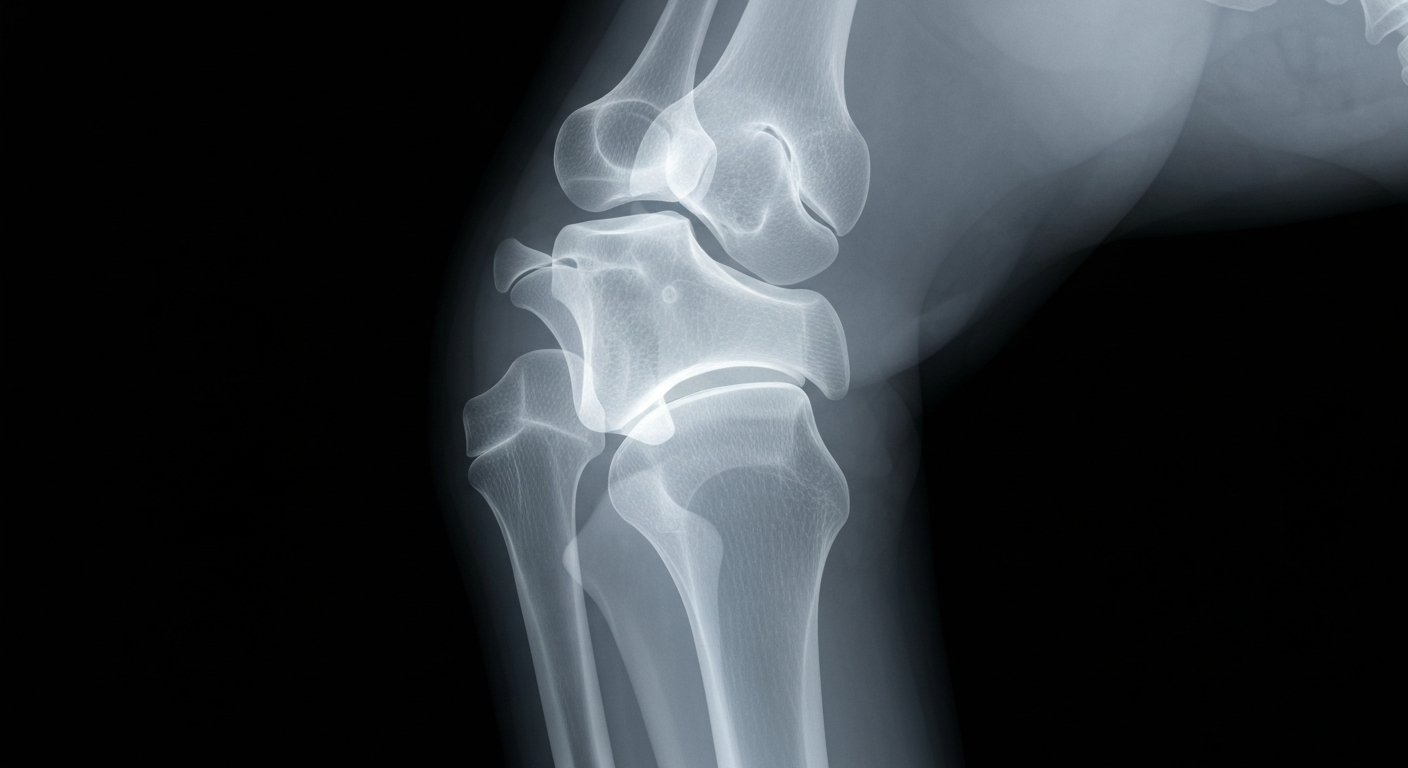

An X-ray image of an orthopedic joint reveals the clinical expertise that Dr. J. Calvin Johnson brings to his work at the intersection of medicine and law.Nichols Hills TodayDr. J. Calvin Johnson, a board-certified orthopedic surgeon and founder of MedLegal Authority, has successfully passed his board recertification examination, extending his certification for an additional ten years. In addition, Dr. Johnson has been selected as a featured speaker at the 51st Annual Orthopedic Surgery Visiting Professor Conference hosted by the University of Oklahoma College of Medicine, where he will present on the critical role of medical documentation in clinical practice and legal proceedings, as well as best practices for physicians serving as expert witnesses.